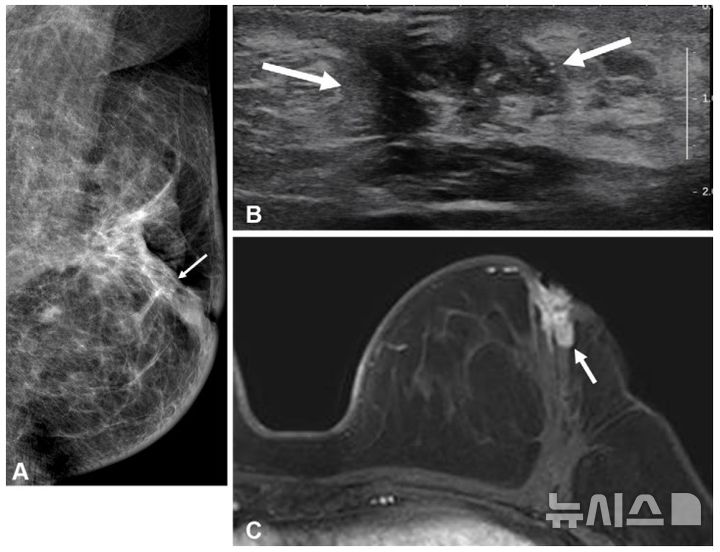

[서울=뉴시스] 수술 후 같은 측 유방 내 재발이 발생한 젊은 유방암 환자의 검사 결과. (사진= 서울대병원 제공)

유방암은 호르몬 수용체 유무에 따라 재발 양상이 다르며, 특히 호르몬 수용체 음성 유방암은 양성 대비 재발률이 높다. 50세 이하 유방암 환자는 유방 조직이 치밀한 경우가 많아 조기 진단이 어려울 뿐 아니라 호르몬 수용체 음성 유방암 발생률이 높다. 또 수술 후 같은측 유방 내 재발(국소 재발) 가능성도 높기 때문에 정확한 진단과 최적화된 수술을 위해 수술 전 '유방 MRI' 사용이 증가하는 추세다.